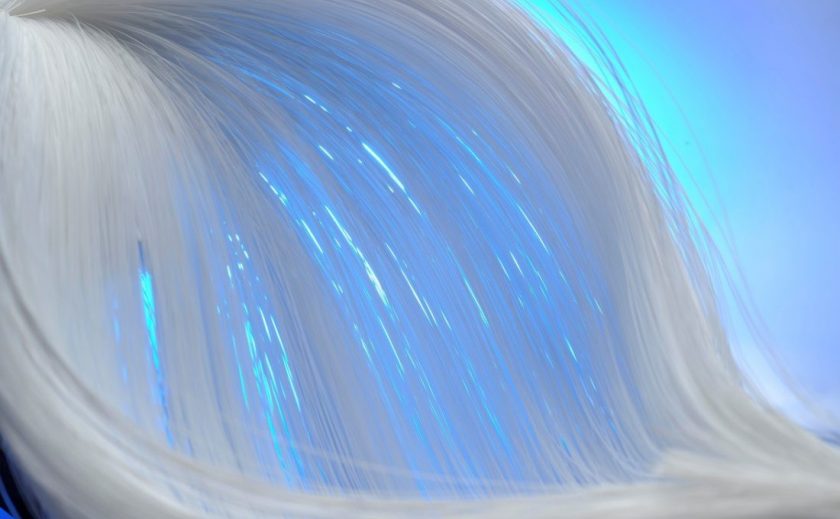

人工心肺のフィルターに使われる中空糸膜

中空糸膜フィルター(写真提供:DIC株式会社)

人工心肺の重要なパーツとして、血液に酸素を送る役割を果たすのが中空糸膜フィルターです。中空糸は、とても細いストロー状の糸の壁に小さな穴がたくさん空いています。中空糸を束ねてフィルターの仕事をするのが中空糸膜フィルターです。

私達の体には動脈と静脈が張り巡ぐらされています。動脈を流れているのは、肺から送り込まれる酸素や肝臓に送られる栄養素を含んだ血液を体の隅々まで送り届けます。静脈は体中の二酸化炭素を回収して、再び肺などへ送り届ける役割を果たします。